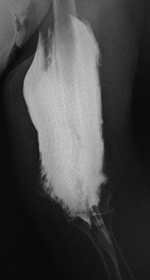

| Frontal and lateral views of the right wrist after placement of a volar T-plate and screws for a comminuted distal radius fracture. On the lateral view there is a retained drill guide (arrow) that was inadvertently left in place. It should have been removed at the end of the surgical procedure. It is not evident on the AP view and was initially overlooked by both an MSK radiologist and the patient's orthopedic surgeon. |